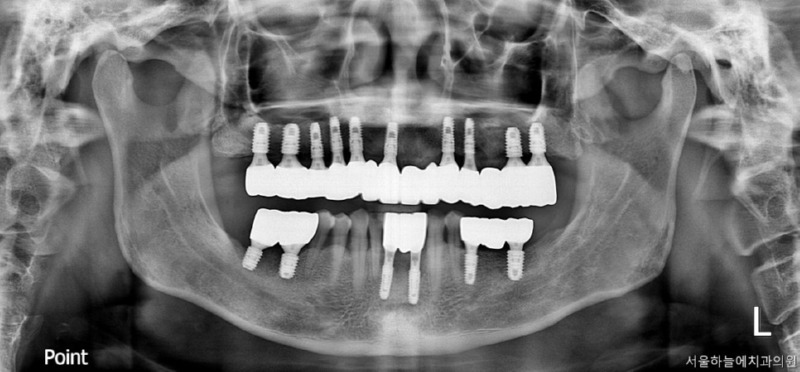

수술 후 4개월

수술 후 6개월 후 보철완료